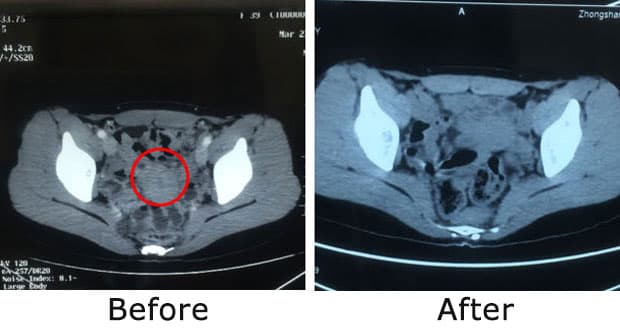

Tim MDT RS kemudian merancang sebuah rencana pengobatan untuknya, termasuk terapi bertarget, terapi natural, dan imunoterapi.

Diana Kartika Arma, kanker serviks stadium IB2B - telah bertahan 3 tahun.